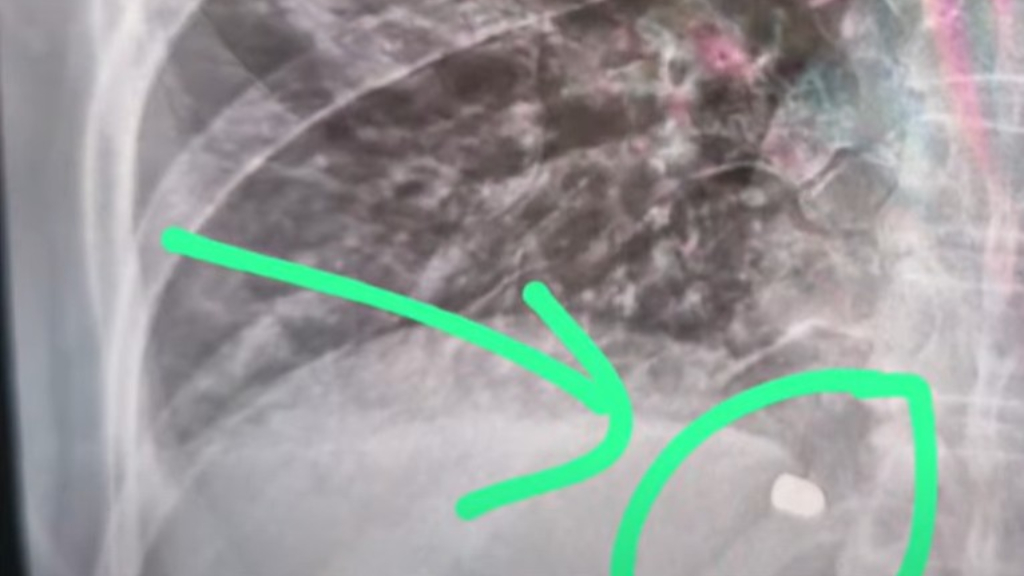

El episodio ocurrió el domingo por la tarde, cuando Ana navegaba por el Arroyo Correntino con un grupo de allegados, desde el río Paraná hacia el río Luján, y recibió un disparo en el pulmón.